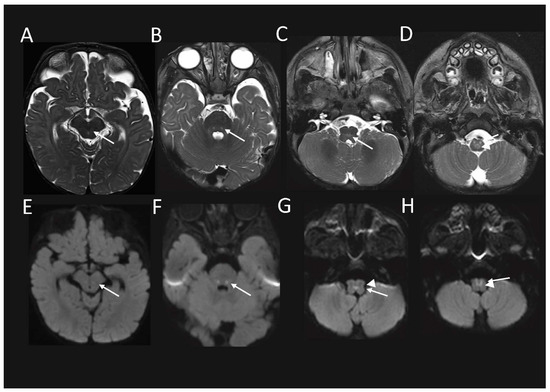

We then explored the dataset and performed gene ontology (GO) enrichment analysis [12,13,14] on the proteins that had significantly different levels (Supplemental Table S3). The 263 proteins of a lower abundance in the patient fibroblasts relative to the control fibroblasts, were analysed by GO enrichment analysis to determine the represented Reactome pathways. The top Reactome pathways of a lower abundance in the patient fibroblasts (Supplemental Table S4) were mitochondrial translation elongation (13.77-fold enrichment, FDR 9.71 × 10−10), mitochondrial translation termination (13.77-fold enrichment, FDR 4.85 × 10−10), mitochondrial translation initiation (13.77-fold enrichment, FDR 3.24 × 10−10), and complex-I biogenesis (11.01-fold enrichment, FDR 5.96 × 10−4). A volcano plot of the significantly altered proteins in the cell lysates (Figure 4A) highlighted both the mitoribosomal proteins involved in the mitochondrial translation (purple) and complex-I biogenesis (blue), which were significantly decreased in the patient cells. We then subset the data and only considered the mitochondrial proteins listed in the MitoCarta 3.0 database [15,16]. A volcano plot reveals the additional mitoribosomal and complex-I proteins as significantly decreased in the patient cells (Figure 4B).

The ratio of each OXPHOS complex subunit in the patient fibroblasts was normalized to that of the controls and showed a significant reduction in complex I (70% abundance) compared to the controls, whilst complexes II, III, IV, and V were normal (Figure 4C). A similar analysis for the mitoribosomal protein subunits of the small subunit (SSU) and large subunit (LSU) revealed a significant reduction in both the SSU and LSU. The topographical heatmapping of relative subunit abundances on to the cryo-electron microscopy structure of the human mitoribosome [17], highlighted that the defect was predominantly restricted to the proteins found within the LSU (Figure 4D)

Figure 4. Quantitative proteomics from patient fibroblasts indicate a complex I and mitoribosome defect. Complex I subunits and proteins belonging to the mitoribosome are decreased in the PYROXD2 patient relative to controls, suggesting a mitoribosome defect. (A) The volcano plot of the whole-cell fibroblast proteins, and the (B) volcano plot of the mitochondrial proteins (filtered in silico from MitoCarta 3.0 annotation) depicting the differences between the PYROXD2 patient and the controls (n = 5). Significance lines were set to log2 = ±1 (equivalent to fold-change ±2) and p-value = 0.05 equivalent. (C) The relative complex abundance (RCA) plot of the OXPHOS complexes and mitoribosome subunits depicting CI, LSU, and SSU defects. The graph represents each complex ratio of PYROXD2/controls with a 95% confidence interval. p-value 0.05, **: p ≤ 0.01, ****: p ≤ 0.0001, ns: non-significant. (D) Topographical mapping of the relative abundances mapped to the mitoribosome structure depicting areas of decreased abundance. PDB id: 3J9M.